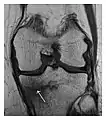

Occult osseous injuries may result from a direct blow to the bone by compressive forces of adjacent bones against one another or by traction forces during an avulsion injury. Lesions in the tibial plateau, hip, ankle, and wrist are often missed. In a tibial plateau fracture, any disruption of the posterior and anterior cortical rims of the plateau should be sought. Impaction of subchondral bone will appear as an increased sclerosis of the subchondral bone (Figure 1). In the hip, posterior acetabular fractures also present subtle radiographic findings. The acetabular lines should then be carefully examined keeping in mind that the posterior rim, which is harder to see on X-rays, is more frequently fractured than the anterior rim (Figure 2). In the wrist, detection of carpal bone fractures is often challenging, with up to 18% of scaphoid fractures radiographically occult. Carpal fractures, especially the scaphoid, are associated with the risk of avascular necrosis. In apparently normal wrist radiographs from symptomatic patients, if there is history of a fall on an outstretched hand with pain in the anatomic snuffbox, suggesting scaphoid injury, the initial examination with posteroanterior, lateral, and pronation oblique views must be complemented by other specific views such as supination oblique and the "scaphoid" view A careful examination of cortices for evidence of discontinuity or offset and cancellous bone for lucency is necessary (Figure 3).[1]

Figure 1: A 56-year-old woman presenting with left knee pain after a fall. (a) Initial anteroposterior radiograph was considered normal, however, subtle cortical disruption of the anterior rim of the medial tibial plateau, medial to the tibial spine, is noted (arrow). (b) Coronal T1-weighted MRI confirms the cortical disruption (arrow) and shows extensive fracture through the proximal tibia. (c) Coronal proton density-weighted image with fat saturation shows extensive edema in the subchondral bone. Note also hypersignal adjacent to the medial collateral ligament corresponding to a grade I sprain (arrowheads).[1]